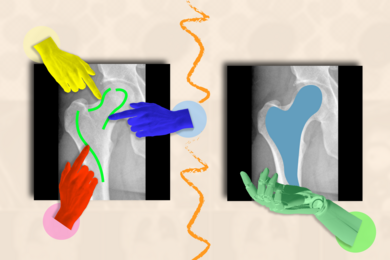

Improving care for people with brain aging diseases requires more than just improvements in understanding pathology and physiology. In his ABI-seeded work, electrical engineering and computer science associate professor Thomas Heldt, a member of the Institute for Medical Engineering and Science (IMES), teamed up with fellow EECS faculty professors Vivienne Sze and Charles Sodini to develop algorithms and software as powerful but unobtrusive ways to monitor patients’ neurocognitive state. Building on studies showing that eye responses exhibit changes in speed and accuracy amid aging and cognitive decline, Heldt’s lab is building a system that enables sophisticated eye tracking measures on common consumer devices such as iPads. These kinds of measures are often taken under carefully controlled lighting and motion conditions in a lab or clinical environment, but that severely limits opportunities for data collection. In their system, volunteers can use an app that asks them to simply glance to one side or another given a cue and measure their reaction time. The software is able to factor out different lighting or motion artifacts that would confound the measurements.